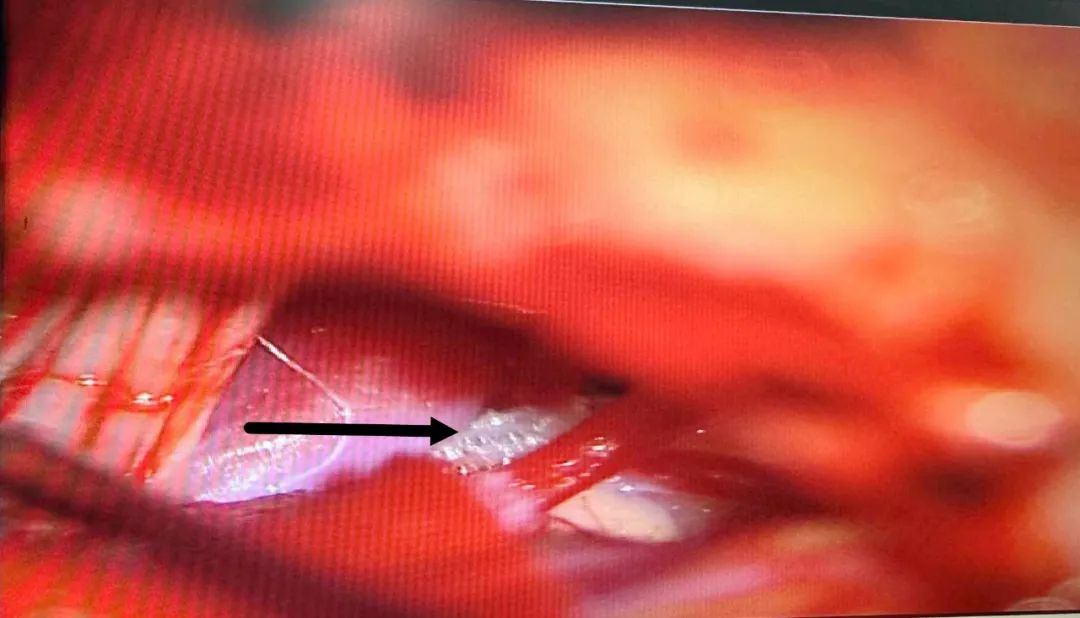

▲脑干处受血管压迫明显

术中,在显微镜的放大作用下,经过精细分离,用特制的器械分离压迫面神经根部的血管,然后放入特制的减压材料将血管与神经隔离开来,并不破坏神经和血管。整个手术过程出血少、时程短,术后未发生任何手术并发症,患者眼睑及面部肌肉再也没有抽搐,整个人的精神面貌焕然一新,目前已康复出院。